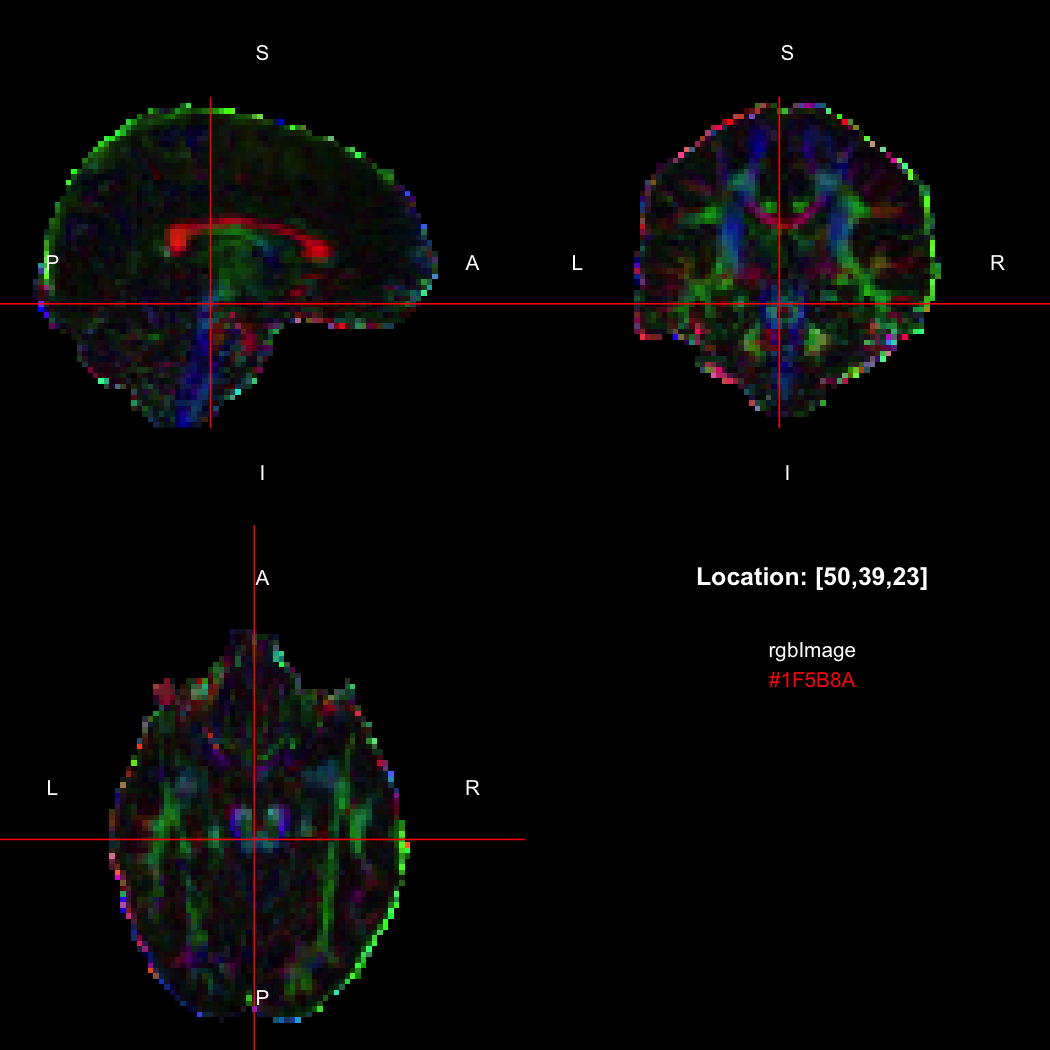

## [1] 300+0iR’s native representation for RGB values is CSS-style hex

strings of character mode, which are reasonably space-efficient (8

or 10 bytes per value) but a little clunky to work with. For efficiency

of interchange between R and the NIfTI-internal datatypes,

RNifti uses a byte-packed representation of integer mode

instead, which takes up 4 bytes per value. Of course, the viewer

understands this format.

rgbImage <- readNifti(system.file("extdata", "example_rgb.nii.gz", package="RNifti"))

print(rgbImage)

## Image array of mode "integer" (2.1 Mb)

## - 96 x 96 x 60 voxels

## - 2.5 x 2.5 x 2.5 mm per voxel

class(rgbImage)

## [1] "niftiImage" "rgbArray" "array"

view(rgbImage)

Notice that values are shown in the viewer using R’s conventional hex

string format, but the data is of class rgbArray. The

function of the same name can be used to create these arrays from

strings or channel values, for the purposes of building RGB images from

data, while the as.character method and

channels function perform the opposite conversions.

as.character(rgbImage, flatten=FALSE)[50,39,23]

## [1] "#1F5B8A"

channels(rgbImage, "red")[50,39,23,1]

## red

## 31RGB images with an alpha (opacity) channel are also supported.